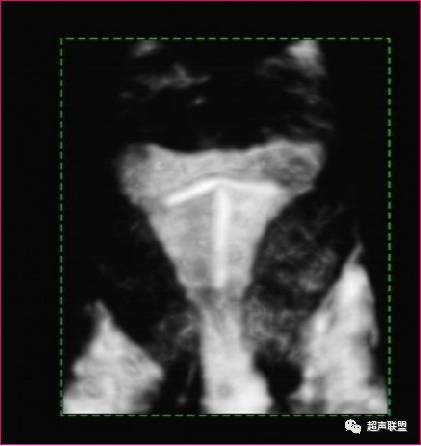

三维超声成像技术可获取二维超声不能得到的冠状面的回声信息,可以直接反映子宫外形和宫腔形态,形象完整地显示IUD的整体,清晰显示IUD有无断裂及嵌顿程度、部位。

同时,因计算机扫描的标准化、程序化,在重建回放检查过程中不易遗漏细节问题,如细碎的IUD残留及与宫壁的关系,从而为临床有的放矢地选择治疗措施提供可靠依据。

诊断:宫内节育环残留可能

宫腔镜证实圆形环宫内残留

(八)、宫内节育器残留

由于各种原因导致取节育器时发生断裂,使节育器一部分遗留在子宫内。

超声图像显示宫腔内或宫肌内见强回声光斑,形态不一,伴彗星尾征,子宫内膜居中或不清。